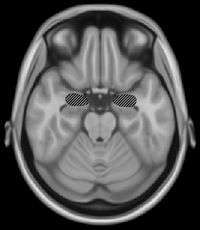

The right secondary auditory cortex has finer pitch resolution than the left. Hyde, Peretz and Zatorre (2008) used functional magnetic resonance imaging (fMRI) in their study to test the involvement of right and left auditory cortical regions in frequency processing of melodic sequences.[12] As well as finding superior pitch resolution in the right secondary auditory cortex, specific areas found to be involved were the planum temporale (PT) in the secondary auditory cortex, and the primary auditory cortex in the medial section of Heschl's gyrus (HG).

Many neuroimaging studies have found evidence of the importance of right secondary auditory regions in aspects of musical pitch processing, such as melody.[13] Many of these studies such as one by Patterson, Uppenkamp, Johnsrude and Griffiths (2002) also find evidence of a hierarchy of pitch processing. Patterson et al. (2002) used spectrally matched sounds which produced: no pitch, fixed pitch or melody in an fMRI study and found that all conditions activated HG and PT. Sounds with pitch activated more of these regions than sounds without. When a melody was produced activation spread to the superior temporal gyrus (STG) and planum polare (PP). These results support the existence of a pitch processing hierarchy.